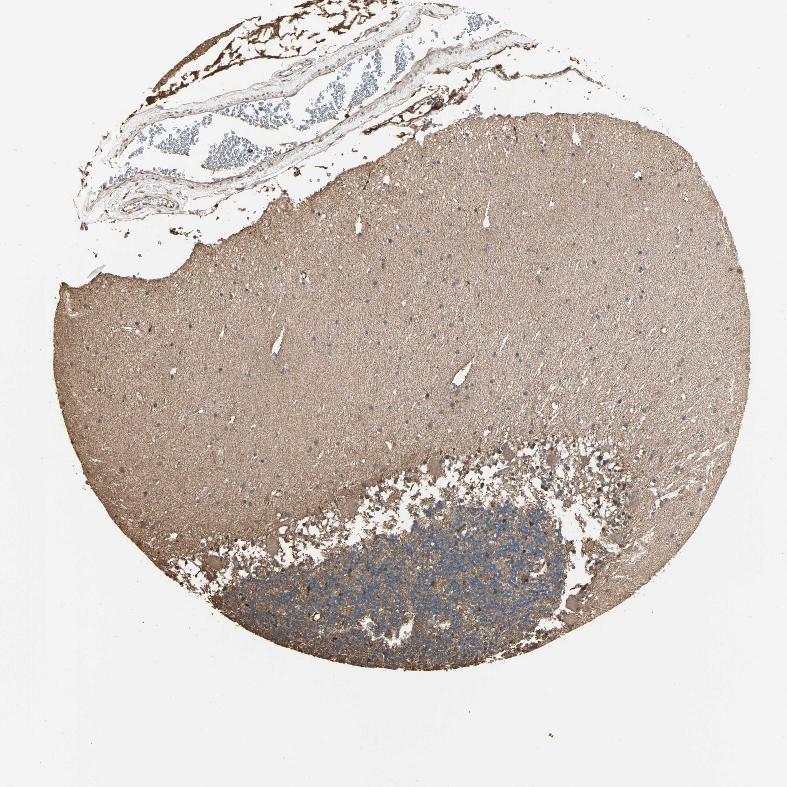

CEREBELLUM - Antibody stainingi

Antibody staining in the annotated cell types in the current human tissue is reported as not detected, low, medium, or high, based on conventional immunohistochemistry profiling in selected tissues. This score is based on the combination of the staining intensity and fraction of stained cells.

Each image is clickable and will lead to virtual microscopy that enables deeper exploration of all samples and also displays staining intensity scores, fraction scores and subcellular localization as well as patient and tissue information for each sample.

Antibody HPA007716

Purkinje cells Low

Cells in granular layer Not detected

Cells in molecular layer Low